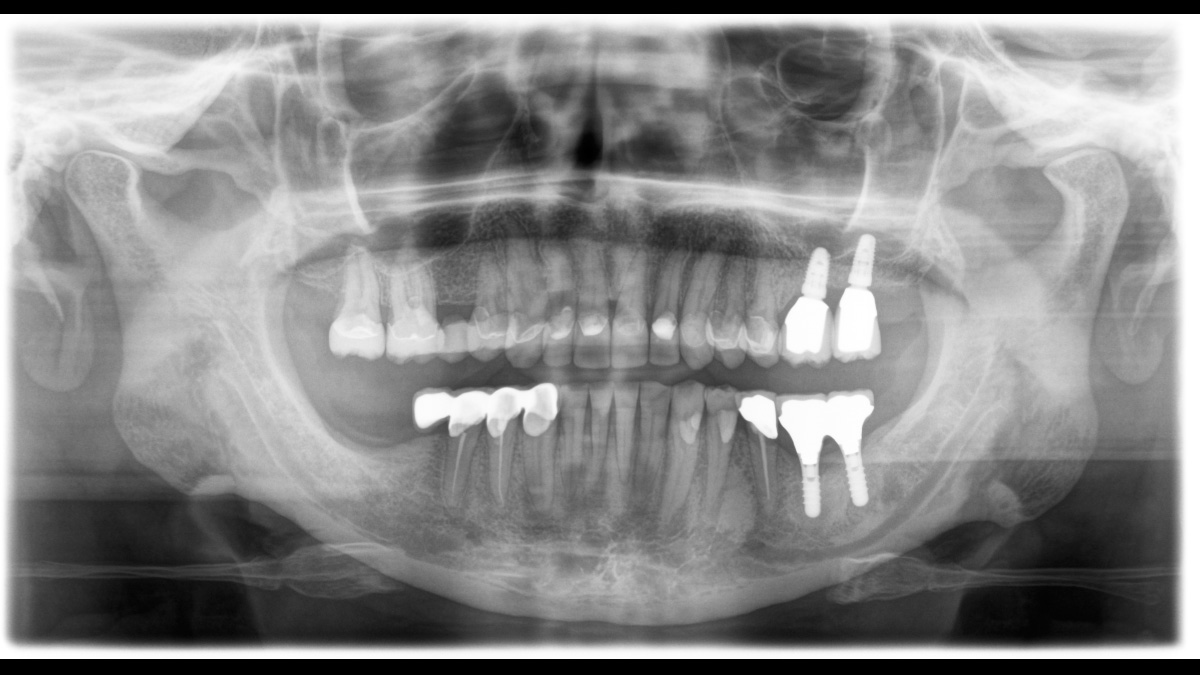

El equipo de radiología 2D/3D de alta calidad con una amplia gama de servicios para cada clínica. Ya sea como un dispositivo puramente 2D o como un módulo 3D, el Orthophos S es un socio confiable y está optimizado para las tareas diarias. Su sensor CsI Plus con función de autofoco garantiza imágenes claras, incluso en casos anatómicamente difíciles. El posicionamiento automático del paciente junto con el bloque de mordida oclusal patentado permite un posicionamiento del paciente fácil y que ahorra tiempo. Para su uso en ortodoncia, la Orthophos S también está disponible con un brazo cefalométrico opcional. Y como para Dentsply Sirona es importante estar preparado para el futuro, el brazo cefalométrico se puede reacondicionar en cualquier momento.

Para la mayoría de las clínicas, se utiliza un equipo de radiología con dos objetivos principales en mente: capturar la mejor imagen posible para respaldar un diagnóstico preciso y exacto, y garantizar que el paciente se sienta cómodo durante el proceso. El Orthophos S ofrece soluciones únicas y patentadas para apoyar ambos objetivos con:

El enfoque correcto es crucial para excelentes radiografías panorámicas. Con la función de autofoco, usted recibirá automáticamente una imagen con la mejor nitidez posible en foco. Los dispositivos de radiología de Dentsply Sirona toman varios miles de imágenes individuales en un ciclo e identifican automáticamente las áreas donde la mandíbula está posicionada de manera óptima. Luego, sin ningún paso manual adicional, estas imágenes se muestran en una nítida imagen final.

El sistema detecta las áreas relevantes a partir de varios miles de imágenes individuales en un ciclo e identifica automáticamente las áreas donde la mandíbula está posicionada de manera óptima.

Imágenes nítidas.